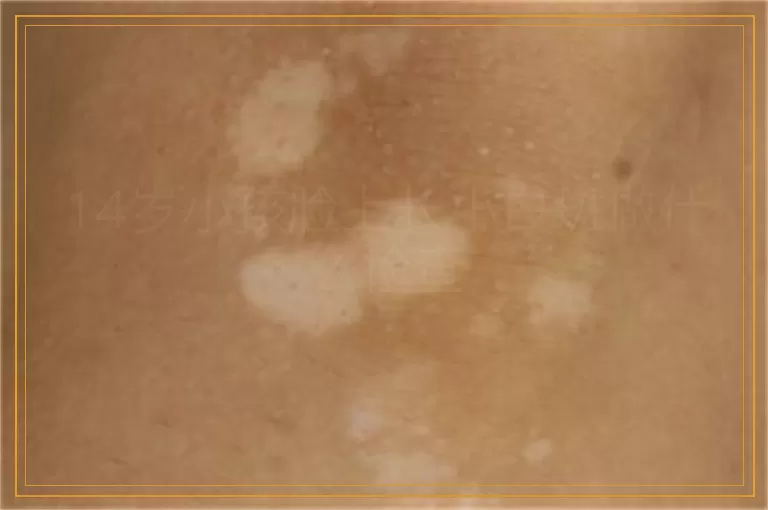

14岁小孩脸上长小白斑做什么检查

14岁的孩子正是爱美的年纪,说不在意脸蛋那是假话。爸妈发现一侧脸颊冒出几块米粒大小的淡淡白斑,不红不肿也不痒,细看才看到边缘有些锯齿感,心里一下就慌了:这是不是白癜风?医生给家长吃个定心丸,先别自己吓自己,脸上小片发白也许是汗斑、单纯糠疹、炎症后色素减退,也可能是早期白癜风,几个检查就能辨出真假。